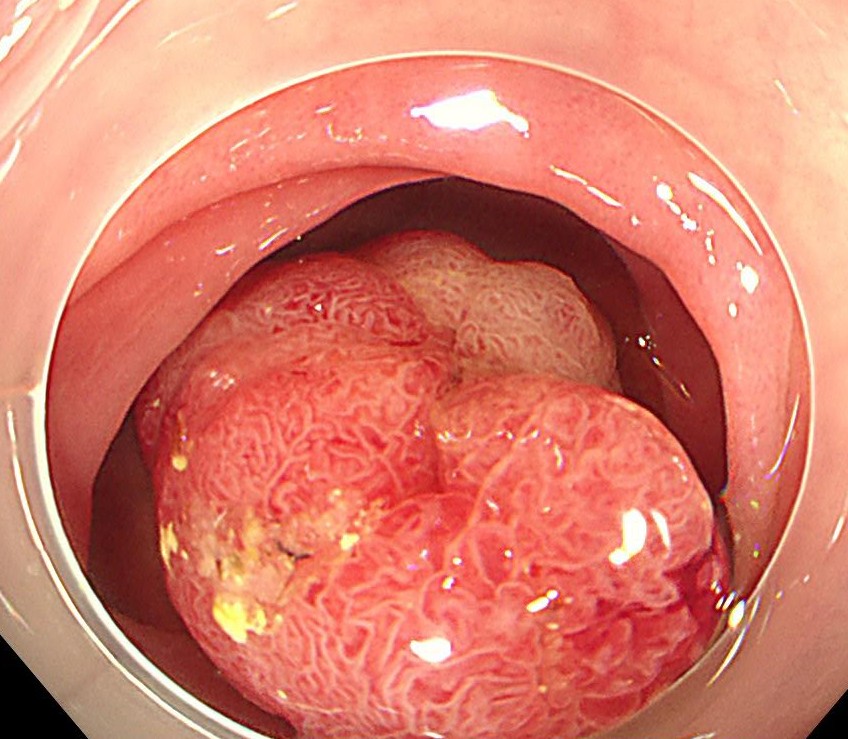

横行結腸に1型の腫瘍を認めます。

ピットパターンはおおむねIII型ですが、腫瘍基部と中心陥凹部はV型であり、早期の大腸がんが疑われます。